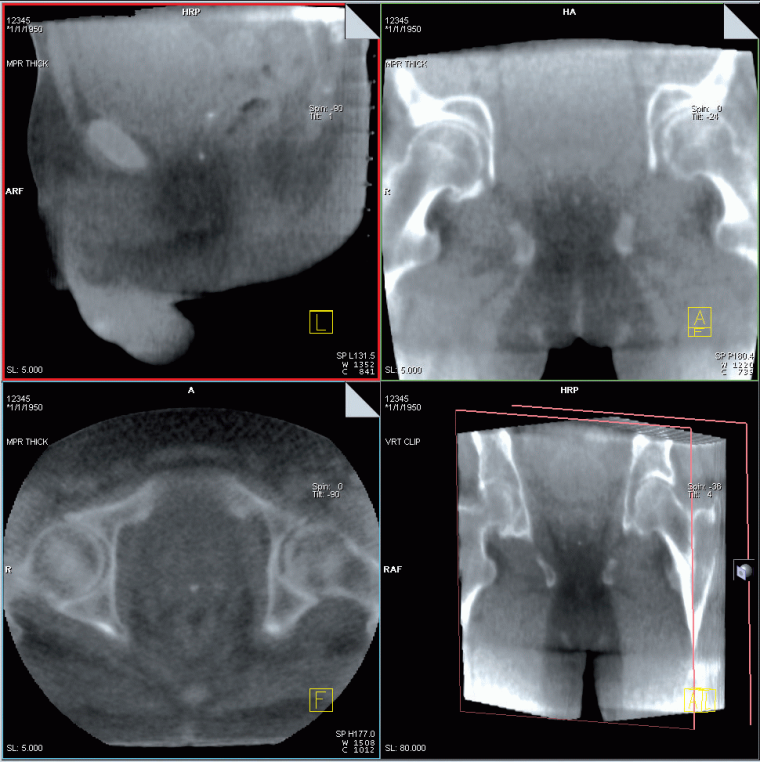

Hierzu dient das Softwarepaket Adaptive Targeting. Adaptive Targeting ermöglicht dem Anwender, die am Linearbeschleuniger erzeugten dreidimensionalen Bilder zu vergleichen mit Bildern, die im diagnostischen bzw. Planungsprozess erstellt und bearbeitet wurden. So kann das aktuelle Tumorvolumen mit einfachen Mitteln mit dem diagnostischen Tumorvolumen verglichen werden.

Durch den Einsatz des hochwertigen Detektors können auch Bereiche im Weichteilkontrast mit MVision erkannt und ausgewertet werden. Bei erkennbaren Veränderungen kann der Prozess der Strahlentherapie sofort darauf abgestimmt werden.